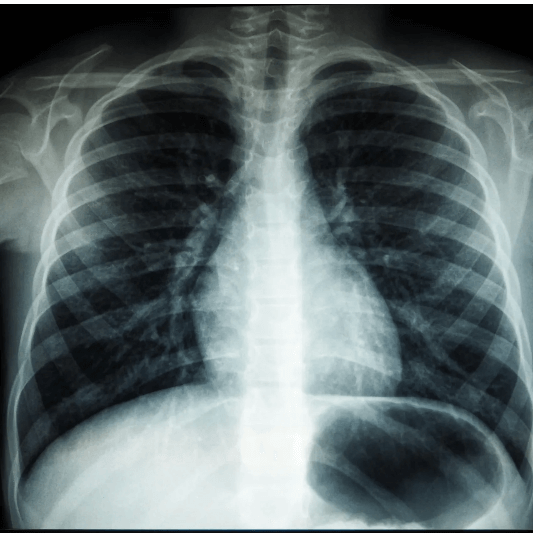

2-2. 전자담배에 포함된 유해물질

전자담배에는 다음과 같은 유해물질이 포함되어 있습니다:

- 니코틴: 뇌 발달에 영향을 미치고 중독성을 유발하는 대표적인 물질

- 다이아세틸: 폐 섬유화 유발

- 중금속: 납, 니켈, 주석 등이 포함되어 장기적 손상 유발

- 휘발성 유기화합물: 호흡기 자극 및 장기 손상

- 발암물질: 장기적인 건강 악화와 연관

이러한 성분들은 단순한 호기심의 대가로 돌이킬 수 없는 건강 피해를 줄 수 있습니다.